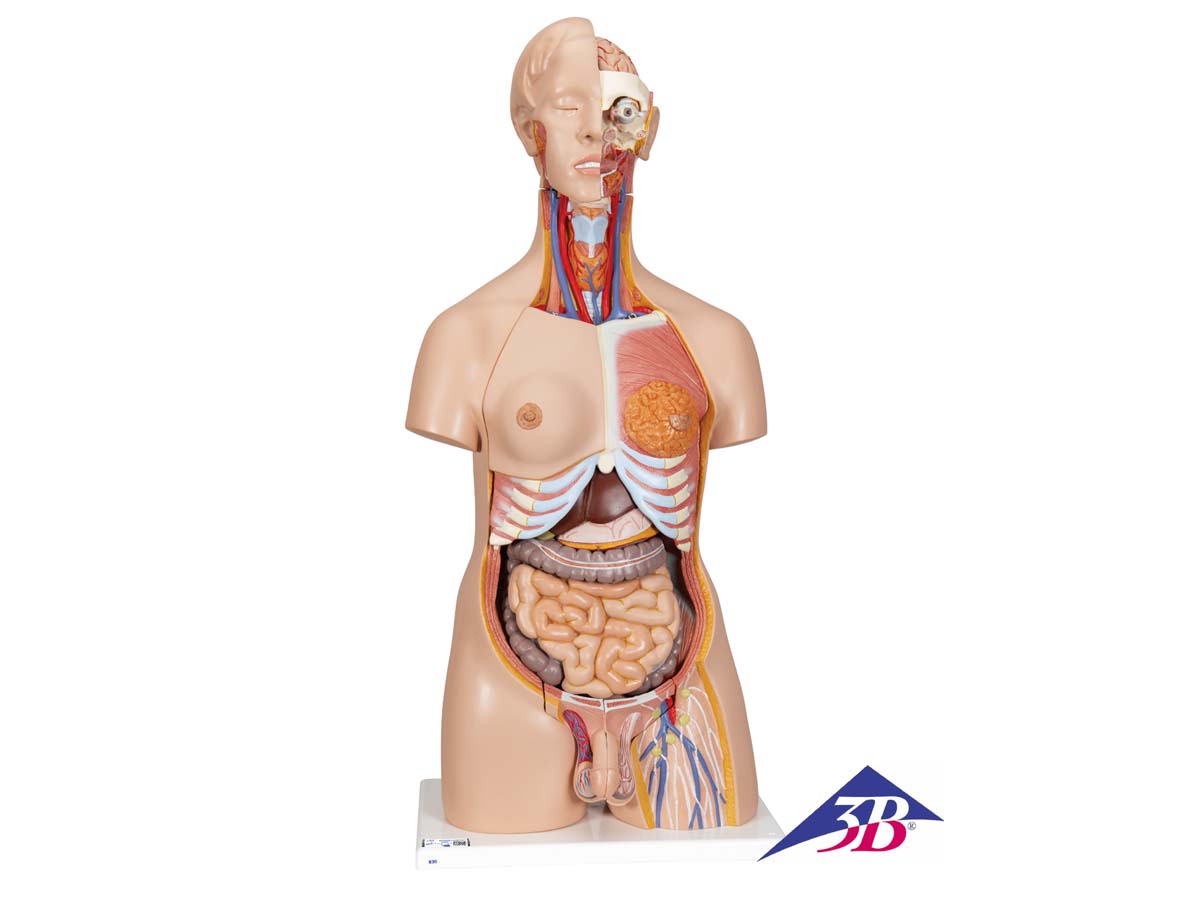

Der 3B Scientific Luxus-Torso bietet Ihnen alle Möglichkeiten für ausführliche Demonstrationen. Sie erhalten hunterprozentige Qualität und einen hohen Grad an Detailarbeit. Die Beschaffenheit der erweiterten Torso-Version ist beeindruckend, genau wie sein Preis! Beantworten Sie mit seiner Hilfe alle Fragen zur inneren Anatomie des Menschen. Er ist zerlegbar in:

– 3-teiligem Kopf

– 2-teiligem Magen

– 4-teiligem Darmpaket

– Weibliche Brustdecke (2-teilig)

– 2 Lungenhälften

– 2-teiliges Herz

– Leber mit Gallenblase

– Vordere Nierenhälfte

– 3-teiliger weiblicher Genitaleinsatz mit Embryo

– 4-teiliger männlicher Genitaleinsatz

Alle Organe in diesem menschlichen Torso sind von Hand bemalt.